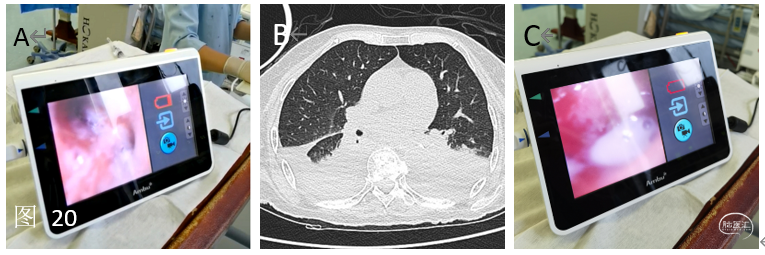

对于手术入路,目前脑血管病的治疗主要经股动脉入路,经桡动脉入路由于患者术后无需卧床,近几年逐渐受到重视,其中经远侧桡动脉入路则最为受到关注。目前,我院可以常规开展远桡入路检查和治疗颅内外脑血管病变(图19)。

对于危重患者的救治:神经重症ICU为术后的危重患者提供全方位的保障,诸如纤支镜吸痰等,上图为医务人员借助纤支镜为脑血管病术后合并肺部感染的重症患者清除痰液。